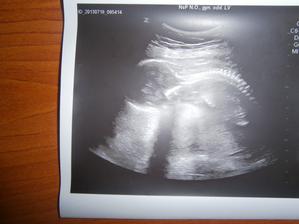

nase babenko v 16tt+3,,a ma 14cm.....tu som a ja sa drzim za hlavicku🙂)

autor@zuzimalinka nospravila aj merania,,,,,takaj som vypitala foto,...a ma 14cm,,,,tak oklolo mam mat az 16cm,,,